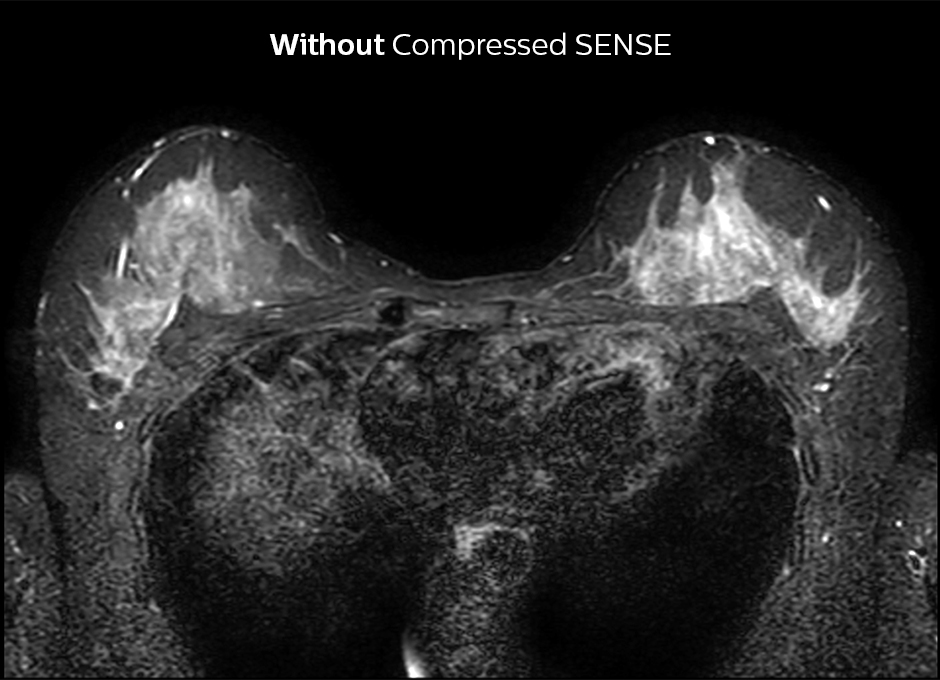

At KSW, Compressed SENSE is also applied to reduce scan time for breast imaging. 2D STIR is now faster and silicon-only sequences are 30% faster, for example. The post-contrast 3D T1 THRIVE can be accelerated by approximately 40% and Compressed SENSE is currently being added to the dynamic T1 sequence, where the goal is to get higher resolution in the same scan time.

Compressed SENSE allows 29% shorter scan time with similar spatial resolution.

2D STIR, scan time 3:39 min, voxel size 1 x 1.25 x 3 mm.

2D STIR, scan time 2:36 min, voxel size 1 x 1.26 x 3 mm.